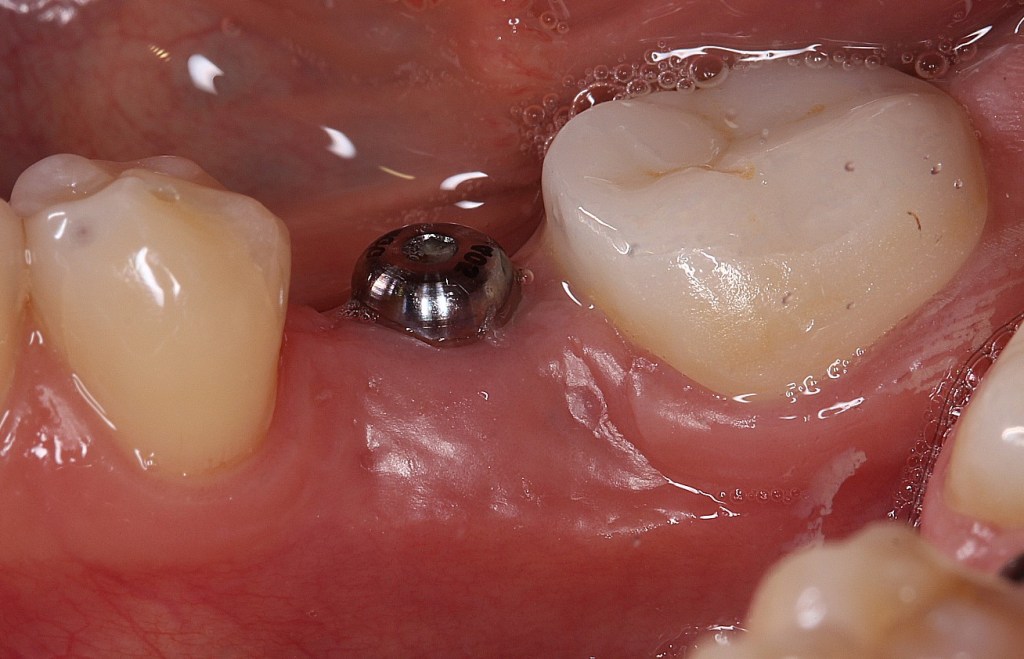

Implant Megagen Anyridge, inserat intr-o creasta atrofica, de 6,5mm latime. Simple anyridge implant placement, with bone expansion and CTG to compensate the 6,5mm bone crest.

Insufficient crest width and thin tissue